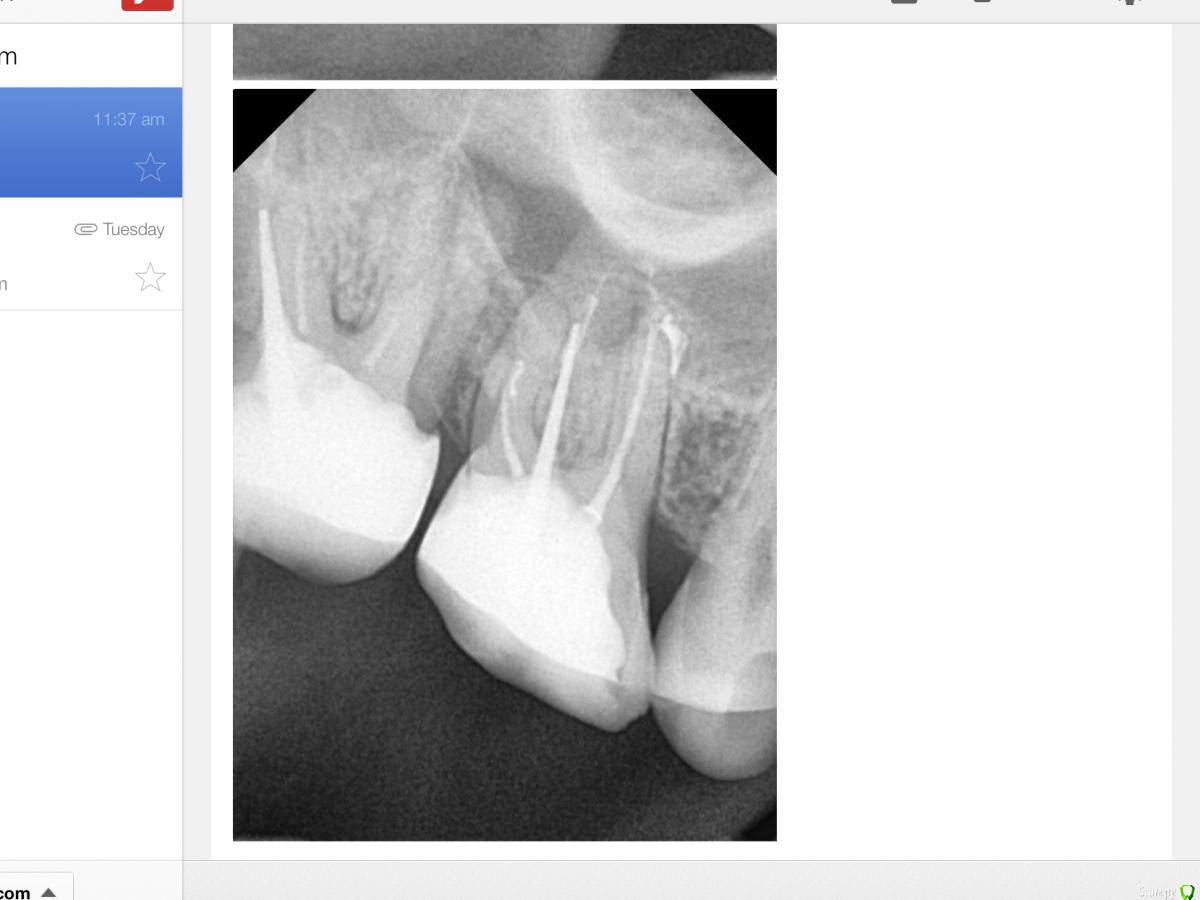

RUVIK Опубликовано 21 декабря, 2018 Автор Поделиться Опубликовано 21 декабря, 2018 Вот прицельные снимки под микроскопом .Что скажите ,стоит ли пробовать перелечивать каналы или шансов нет? Ссылка на комментарий

RUVIK Опубликовано 21 декабря, 2018 Автор Поделиться Опубликовано 21 декабря, 2018 (изменено) Вот прицельные снимки под микроскопом .Что скажите ,стоит ли пробовать перелечивать каналы или шансов нет? Изменено 21 декабря, 2018 пользователем RUVIK Ссылка на комментарий

DmitrySH Опубликовано 21 декабря, 2018 Поделиться Опубликовано 21 декабря, 2018 Нормальные шансы 1 Ссылка на комментарий